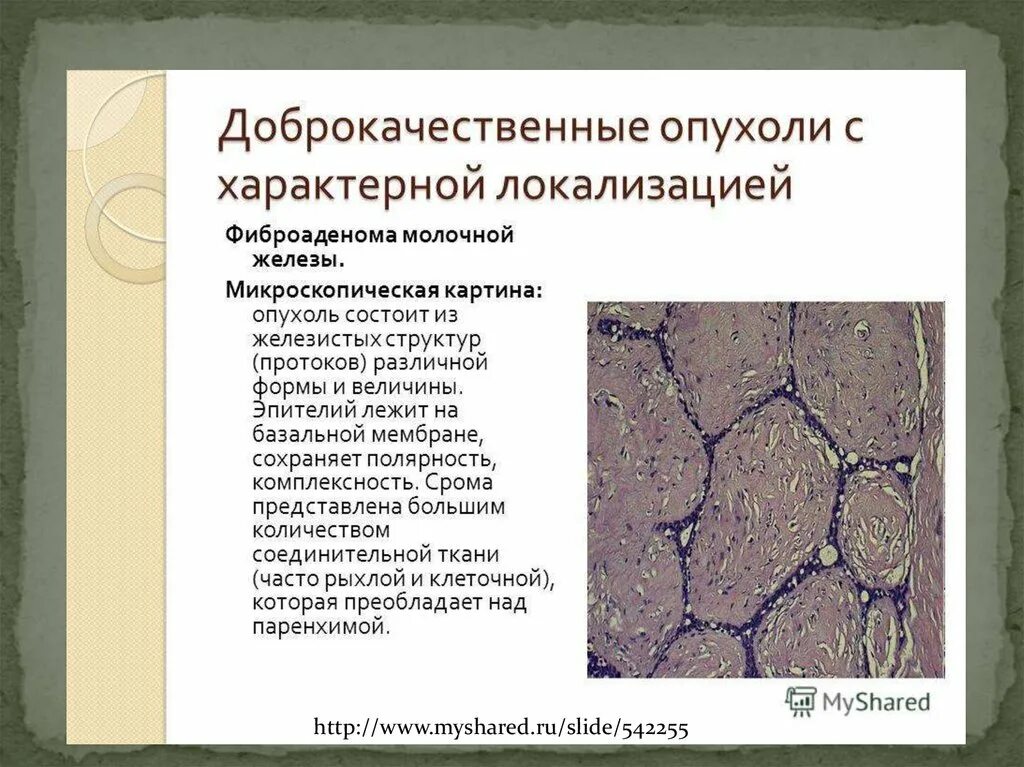

Новообразование в головном мозге. Презентация опухоль мозга. Опухоли головного мозга презентация. Злокачественная фиброаденома молочной железы. Фиброаденома молочной железы Размеры для операции. Фиброаденома молочной железы маммография. Листовидная опухоль гистология.

Злокачественная фиброаденома молочной железы. Фиброаденома молочной железы Размеры для операции. Фиброаденома молочной железы маммография. Листовидная опухоль гистология. Доброкачественная опухоль. Доброкачественныеопкхоли. Клетки, образующие доброкачественную опухоль:. Строение доброкачественной опухоли.

Доброкачественная опухоль. Доброкачественныеопкхоли. Клетки, образующие доброкачественную опухоль:. Строение доброкачественной опухоли. Гиповаскулярные метастазы печени кт. Опухоль желудка метастазирование.